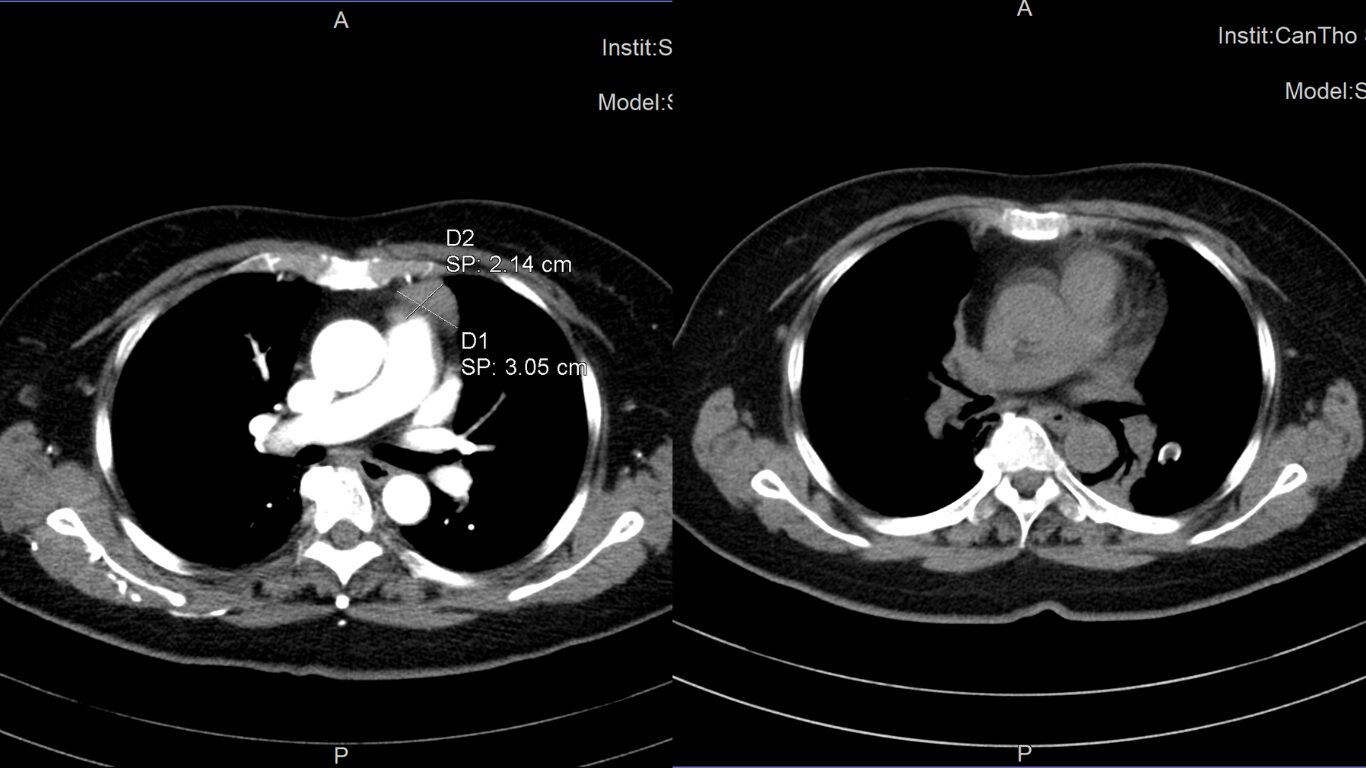

Hình ảnh khối u tuyến ức của bệnh nhân trước và sau khi mổ